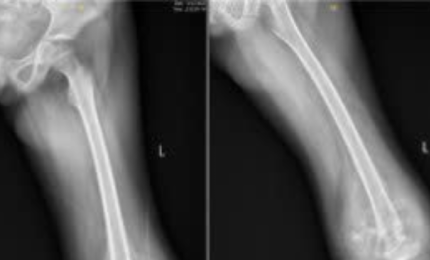

Bé trai được phát hiện ung thư nguy hiểm từ một dấu hiệu ở chân

Bé trai 10 tuổi sưng đau gối kéo dài, khi đi khám phát hiện bệnh ung thư.